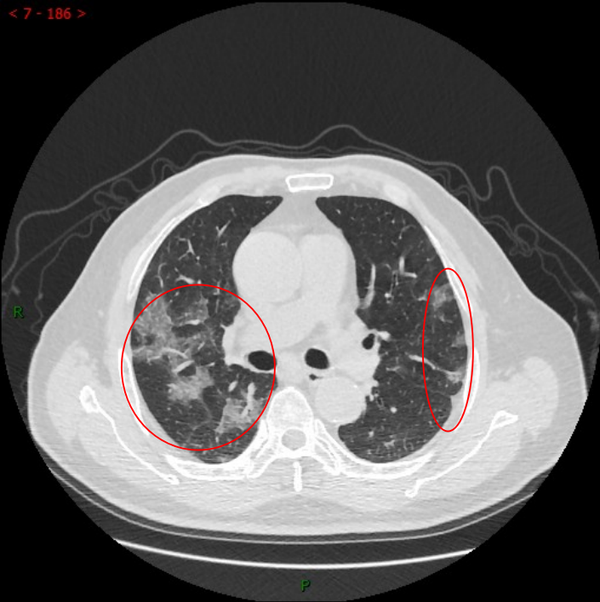

胸部ct白肺?? - 急救与危重病讨论版 -丁香园论坛

图片尺寸2976x3968